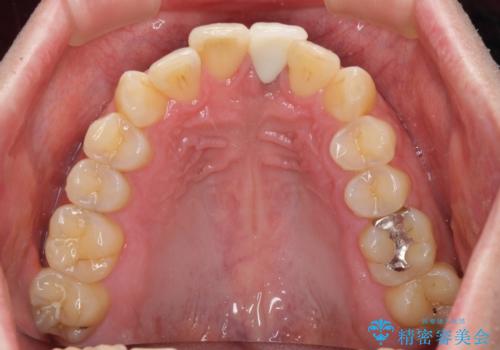

インプラントが唇側に埋入されており、セラミッククラウンの歯肉ラインが左右非対称となっていました。

仮歯は両サイドの歯と接着剤で止められており、接着が著しく変色していたため、セラミッククラウンが装着されて自然な口元となりました。